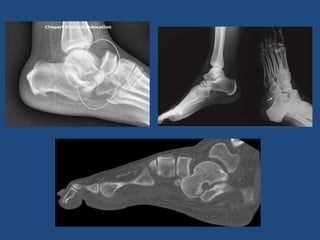

Fx-Lux Chopart

• Infrecuentes

• Alta energía o

torsión

deportistas/bailarin

es

• Ojo esguinces con

mucha clínica

• Exploración clínica parecida a Lisfranc.

• Ojo Sdme compartimental

• Tratamiento parecido al Lifranc

• Secuelas: Artrosis postraumática